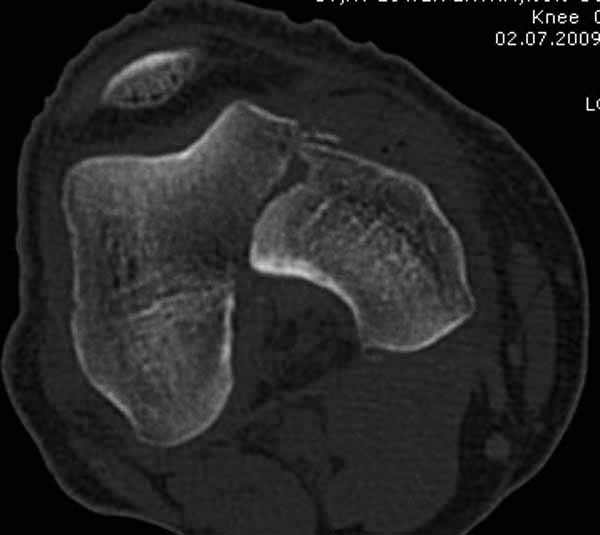

>Сразу не обратил ваше внимание именно на это, что сломаны оба мыщелка, и больший является именно медиальным мыщелком

А теперь по поводу лечения перелома. Среди всех чрез/меж-мыщелковых переломов в 38% сопровождются переломом в корональной плоскости, т.е перелом Hoffa. Nork et al, J Orthop Trauma, 87:564, 2005.

У больных как в этом случае, с вовлечением двух мыщелков правильно, что сделали вытяжение до операции. Здесь имеется флексионный компонент на другой стороне, и я бы рекомендовал операцию делать из двух доступов. Сперва фиксировать медиальную колонну custom made пластиной, обычно 1/3 тубулярной пластиной в 4.5 мм, потому что пока производители опаздывают с медиальной пластиной.